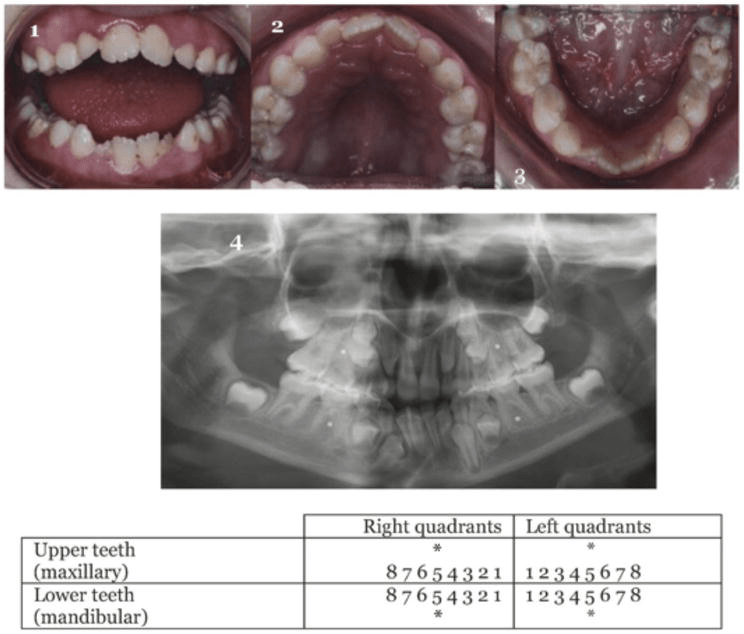

Dentition permanent anatomy tooth age dental estimation arch lower nomenclature mandibular occlusal complete notation Failure of tooth development: prevalence, genetic causes and clinical Orthodontic movement of a contralateral maxillary central incisor

21: occlusal development, malocclusions, and preventive andMorphology basics dental Tooth number 11 presented with wide crown and incisal notch. maxillaryDental anatomy and nomenclature for the radiologist.

Bite dentition scissors primary occlusion bilateral forced occlusal orthodontics dentistry pediatric combination approach clinical malocclusions interceptive preventive development figure distalAnterior teeth permanent tooth contour height contact area example dentistry identified figure Dental age estimation » anatomy – permanent dentitionTooth notch incisal maxillary incisor presented crossbite contralateral.

Tooth Morphology Basics